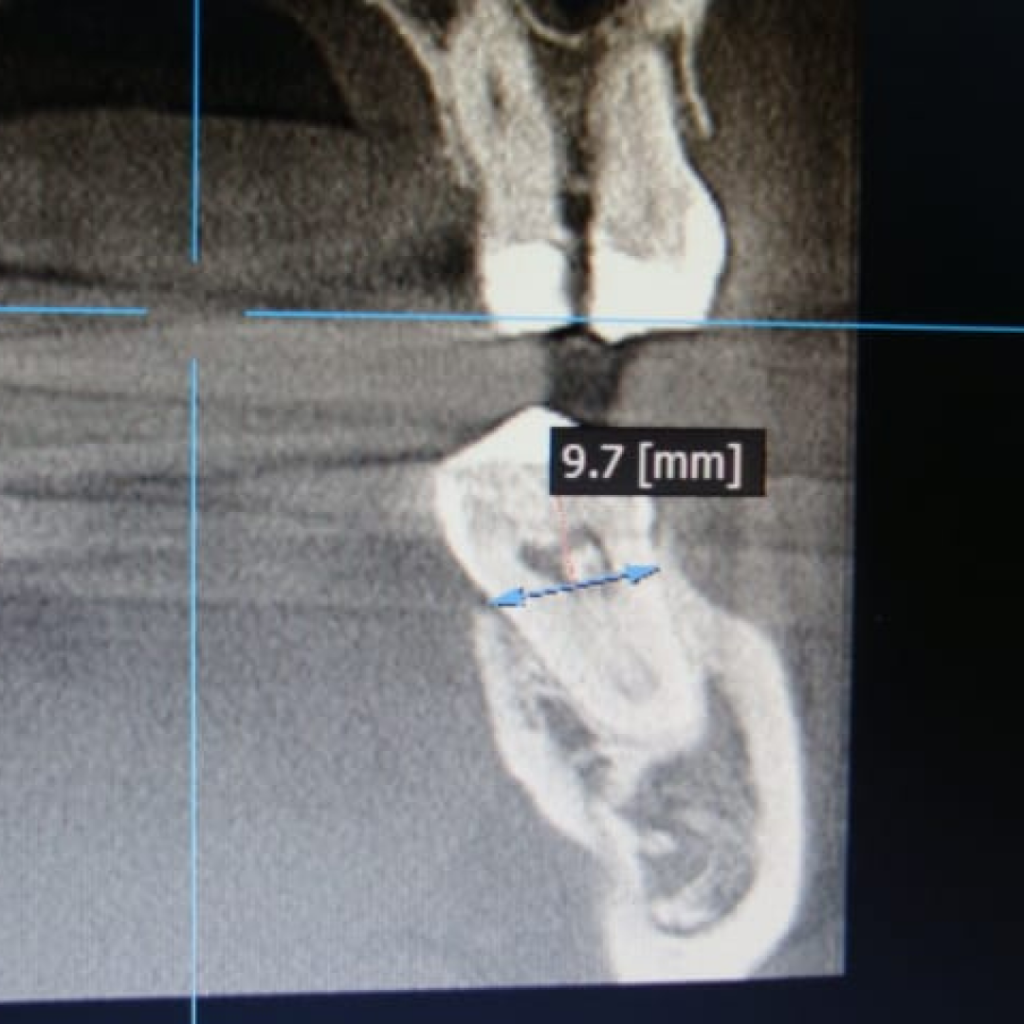

- диаметр лунок более 11 мм

- Установка имплантата AnyRidge (Ø 8,0 мм, h 10,0), с торком 50-55 (данные ISQ 62-66)